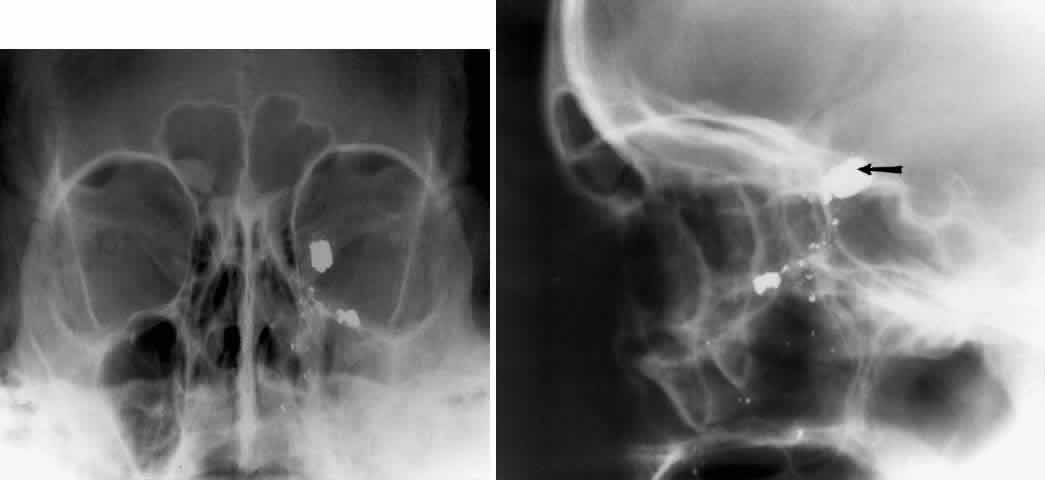

Foreign bodies of the eye or orbit can be detected with plain films. Although standard radiography should theoretically be able to visualize metallic fragments as small as 0.1 mm by 0.1 mm by 0.1 mm,30 a 1991 retrospective study reported lower actual sensitivities: In patients with a high clinical suspicion for an orbital or ocular foreign body, plain radiographs showed a 90% sensitivity for metallic foreign bodies, 71% sensitivity for glass, and lower sensitivities for wood and other materials. Metallic foreign bodies in the cornea showed a particularly high false-negative rate.30,31

CT is now generally regarded as the imaging method of choice to identify suspected foreign bodies in the globe or orbit. A laboratory study comparing plain radiography with CT demonstrated that plain films clearly visualized iron, graphite, and glass (containing trace lead) but could not distinguish between the three. CT, on the other hand, not only was able to distinguish between iron, graphite, and glass but was significantly more sensitive to wood and plastic.32

The localization of foreign bodies with plain films is a recurring challenge. Echography and CT have diminished the need for plain film techniques for localization of foreign bodies, but the latter can be used when other imaging modalities are unavailable. Frontal and lateral projections are standard views in these studies (Fig. 18). Localization of a foreign body within the globe is possible with bone-free examination using dental film or by ocular rotation. This latter study localizes the foreign body to either the anterior or posterior segment of the eye. If the foreign body is anterior, the object will rotate in the same direction as the eye. The object will move in an opposite direction to eye movement if its location is in the posterior segment of the eye33 (Fig. 19). Pfeiffer34 and Worst35 used contact lenses as reference devices in localizing foreign bodies. These techniques are less commonly used.

Fig. 18. Foreign body localization using a frontal and lateral projection. A. Caldwell projection of a patient with a gunshot injury to the left orbit. B. Lateral projection with a large metal fragment (arrow) in the orbital apex.

Fig. 19. Foreign body localization using the ocular rotation technique. The patient is directed to look up, as in A, which shows the foreign body moving in the direction of upgaze. B. Foreign body is seen in an inferior location after the patient looked down. This foreign body was located in the anterior segment of the eye.